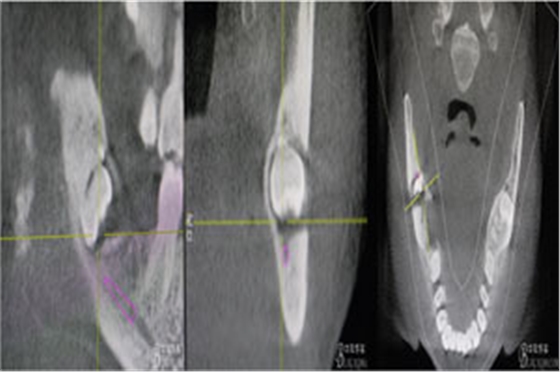

圖3.其他方向的影像檢查:48近中牙冠與下頜管之間無骨壁相隔。